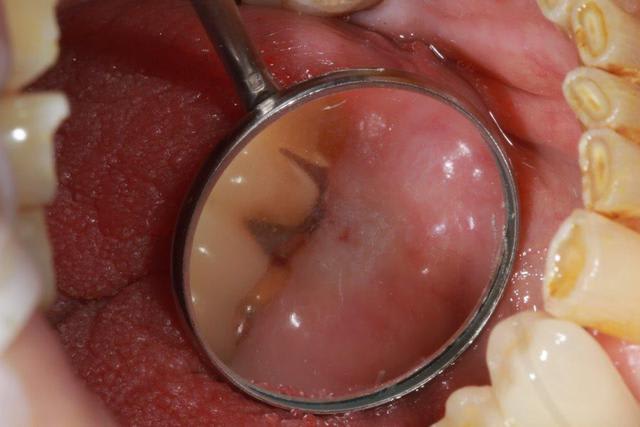

Nouveau patient, pose d'un implant il y a 2 mois....échec sans raisons particulières, douleurs et dépose.

Ce matin repose d'un nouvel implant et comme je ne veux pas prendre de risque, et que les dents adjacentes doivent être couronnées, je pose un bridge en emax press, mais scellé au ciment provisoire...

Si l'implant va bien le bridge sera déposé, coupé, et 44/46 seront collées définitivement après traitement acide et silane.

Si par hasard l'implant pose problème, dépose et bridge collé.